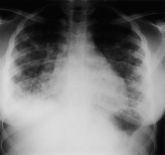

Biến chứng có thể viêm não, viêm màng não, viêm phổi nặng, nhiễm trùng huyết,…dẫn đến tử vong. Nếu tổn thương vào các dây thần kinh sẽ gây mù mắt, liệt mặt, mất vị giác do tổn thương vào dây thần kinh số VII, viêm não khi có tổn thương não. Nếu phụ nữ mang thai mắc bệnh, có thể ảnh hưởng đến thai nhi (như đã đề cập ở trên);